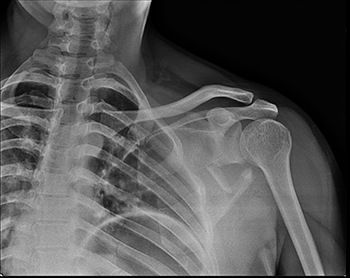

Рентген лопатки

Лопатка — это кость плечевого пояса, которая имеет треугольную форму и соединяет кость плеча с ключицей. Она выполняет двигательную и защитную функцию и иногда может быть повреждена и стать источником серьёзных болевых ощущений и ограничения в движениях. Рентген лопатки — неинвазивный диагностический метод, направленный на визуализацию её костных структур посредством рентгеновских лучей. Он хорошо известен и широко распространён, не требует много времени на проведение и позволяет получить снимки сразу же после проведения процедуры. Другие преимущества заключаются в безболезненности и доступной стоимости.

Что показывает рентген лопатки?

Данный метод диагностики не случайно называют высокоинформативным — он позволяет получить целый ряд важных для постановки диагноза данных:

• Расположение лопаточной кости относительно смежных суставов и костей плеча;

• Наличие/отсутствие изменений в размерах межсуставных щелей, позволяющие сделать выводы о состоянии хрящей и сухожилий;

• Костные структуры и их особенности;

• Трещины, вывихи и переломы;

• Области некротического поражения.

При переломах лопатки важно правильно определить класс перелома, и рентген в данном случае является незаменимым. Важно понимать, что подобные травмы случаются крайне редко, поскольку лопаточная кость очень прочна. Соответственно, лечение в большинстве случаев оказывается длительным и очень непростым. Нередко даже после его окончания в течение некоторого времени пациент испытывает боли при движении верхними конечностями.